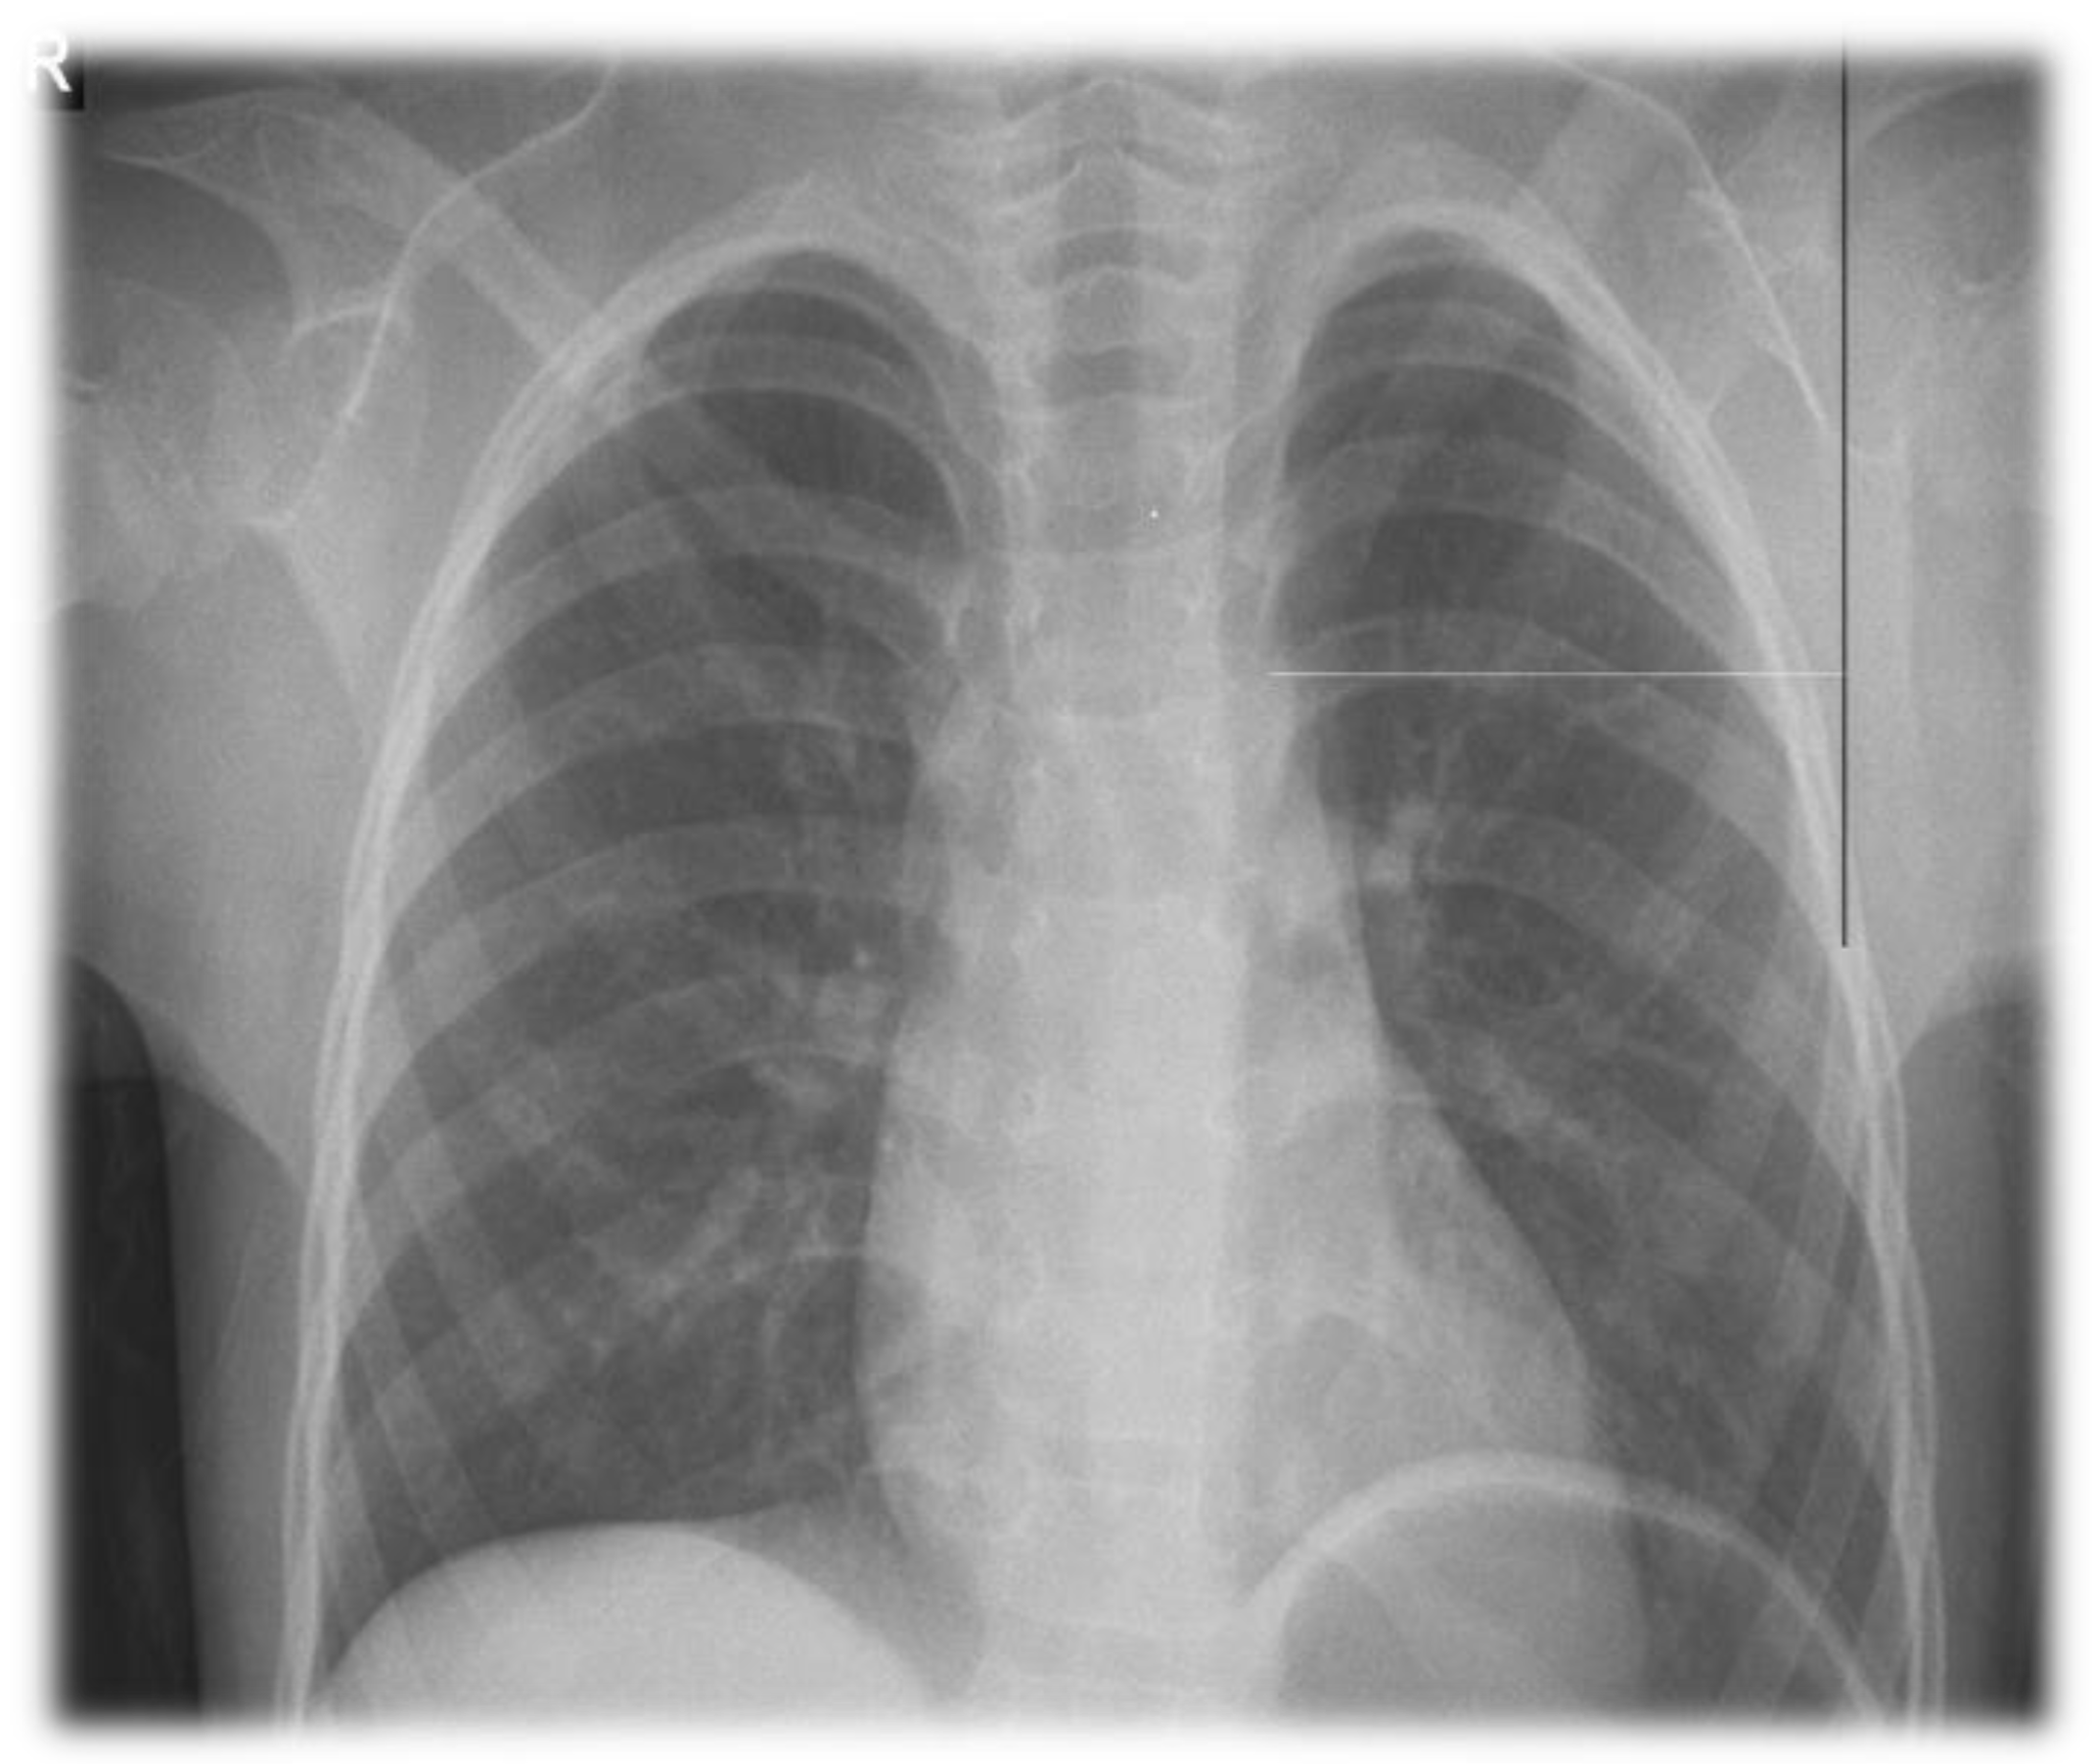

2.5. Screening for Comorbidities